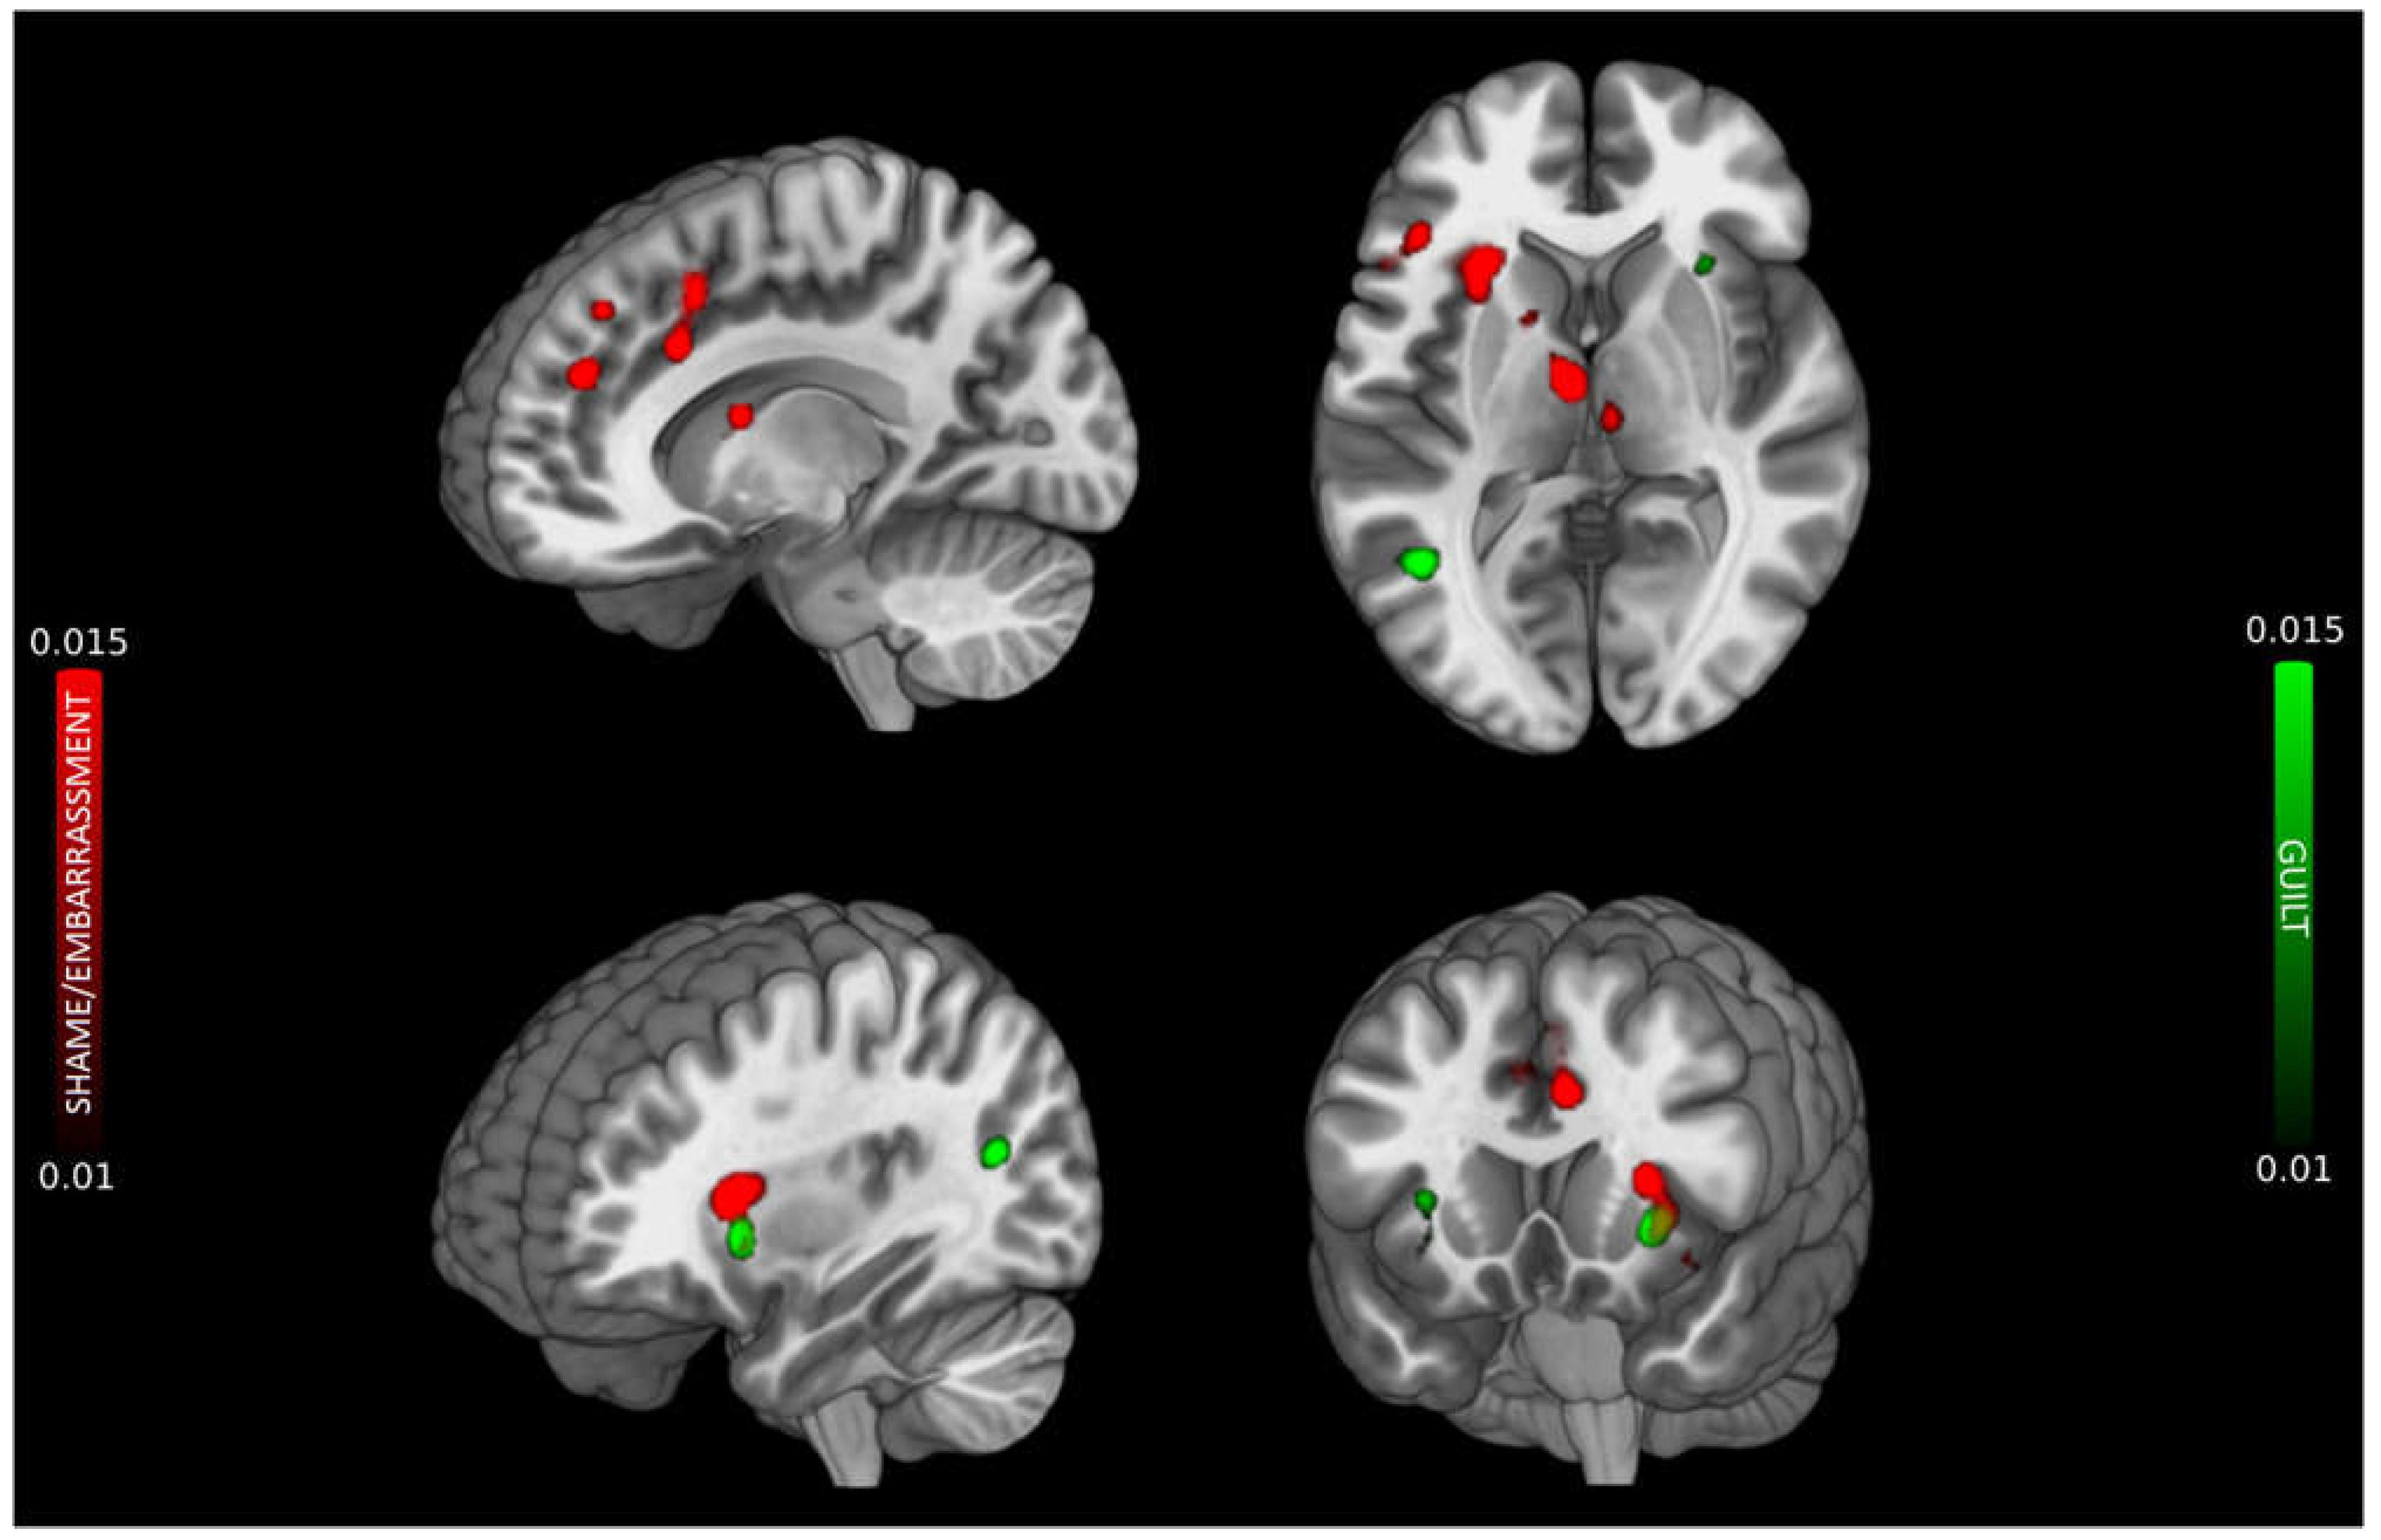

3.1. Shame/Embarrassment

3.2. Guilt

3.3. Conjunction and subtraction analyses

| Cluster # | Volume (mm^3) | Extrema Value | Coordinate | Side | Anatomical Label | BA | ||

|---|---|---|---|---|---|---|---|---|

| x | y | z | ||||||

| 1 | 3896 | 27.37 | -28 | 22 | 8 | Left | Anterior Insula | |

| 17.81 | -36 | 20 | -8 | IFGorb | 47 | |||

| 2 | 2064 | 21.19 | -10 | 44 | 26 | Left | Medial frontal gyrus | 9 |

| 19.53 | -20 | 36 | 36 | Superior frontal gyrus | 9 | |||

| 17.05 | -6 | 38 | 42 | Medial frontal gyrus | 8 | |||

| 3 | 1976 | 29.51 | -6 | -10 | 10 | Left | Thalamus | |

| 18.24 | -14 | 4 | 14 | Left | Caudate | |||

| 15.41 | 6 | -20 | 6 | Right | Thalamus | |||

| 4 | 1688 | 22.70 | -6 | 14 | 44 | Left | Pre-SMA | 6 |

| 22.57 | -6 | 14 | 48 | Pre-SMA | 8 | |||

| 20.21 | -8 | 18 | 32 | dACC | 32 | |||

| 5† | 1016 | 16.64 | 4 | -2 | 34 | Right | dACC | 24 |

| 16.45 | 4 | 16 | 36 | dACC | 32 | |||

| 6† | 976 | 17.42 | -42 | 28 | 16 | Left | Middle frontal gyrus | 46 |

| 13.98 | -52 | 20 | 12 | IFGtri | 45 | |||

| 7† | 960 | 25.41 | 42 | 30 | 14 | Right | Middle frontal gyrus | 46 |

| 8† | 832 | 21.25 | 44 | 2 | 30 | Right | Precentral gyrus/IFGop | 9 |

| Cluster # | Volume (mm3) |

ALE value (*103) |

Coordinates | Side | Anatomical label | BA | ||

| 1 | 1528 | 23.42 | -32 | 18 | -2 | Left | Anterior insula/IFGorb | 47 |

| 2 | 1080 | 20.34 | -44 | -58 | 16 | Left | Superior temporal gyrus | 22 |

| 3† | 848 | 14.65 | 30 | 20 | 4 | Right | Anterior insula | |

| 11.04 | 32 | 16 | -10 | |||||

| 10.81 | 28 | 16 | -6 | |||||

| Shame/embarrassment and Guilt | ||||||||

| Cluster # | Volume (mm3) | ALE value (*103) | Coordinates | Side | Anatomical label | BA | ||

| 1 | 1160 | 18.76 | -34 | 18 | 0 | Left | Anterior insula/IFGorb | 47 |

| Shame/embarrassment vs. Guilt | ||||||||

| Cluster # | Volume (mm3) | Z-scores | Coordinates | Side | Anatomical label | BA | ||

| 1 | 1280 | 2.56 | 0 | -10 | 12 | Left | Thalamus | |

| 2.14 | -10 | 2 | 14 | Caudate | ||||

| 2 | 1280 | 3.06 | -30 | 20 | 14 | Left | Anterior insula | |

| 3 | 1200 | 2.56 | -8 | 17 | 43 | Left | dACC | 32 |

| 1.98 | -10 | 14 | 48 | Pre-SMA | 6 | |||

| 4 | 1000 | 3.06 | 0 | 4 | 36 | Right | dACC | 24 |

| 5 | 960 | 2.36 | 40 | 28 | 18 | Right | Middle frontal gyrus | 46 |

| 2.07 | 44 | 32 | 8 | IFGorb | 46 | |||

| 6 | 688 | 3.24 | -39 | 28 | 17 | Left | Middle frontal gyrus | 46 |

| 7 | 672 | 2.44 | -18 | 32 | 36 | Left | Middle frontal gyrus | 8 |

| 2.18 | -14 | 38 | 34 | Superior frontal gyrus | 9 | |||

| 2.13 | -20 | 40 | 36 | Superior frontal gyrus | 9 | |||

| 8 | 536 | 2.12 | 48 | 1 | 29 | Right | Precentral gyrus | 6 |

| 1.89 | 46 | 3 | 36 | Precentral gyrus | 6 | |||